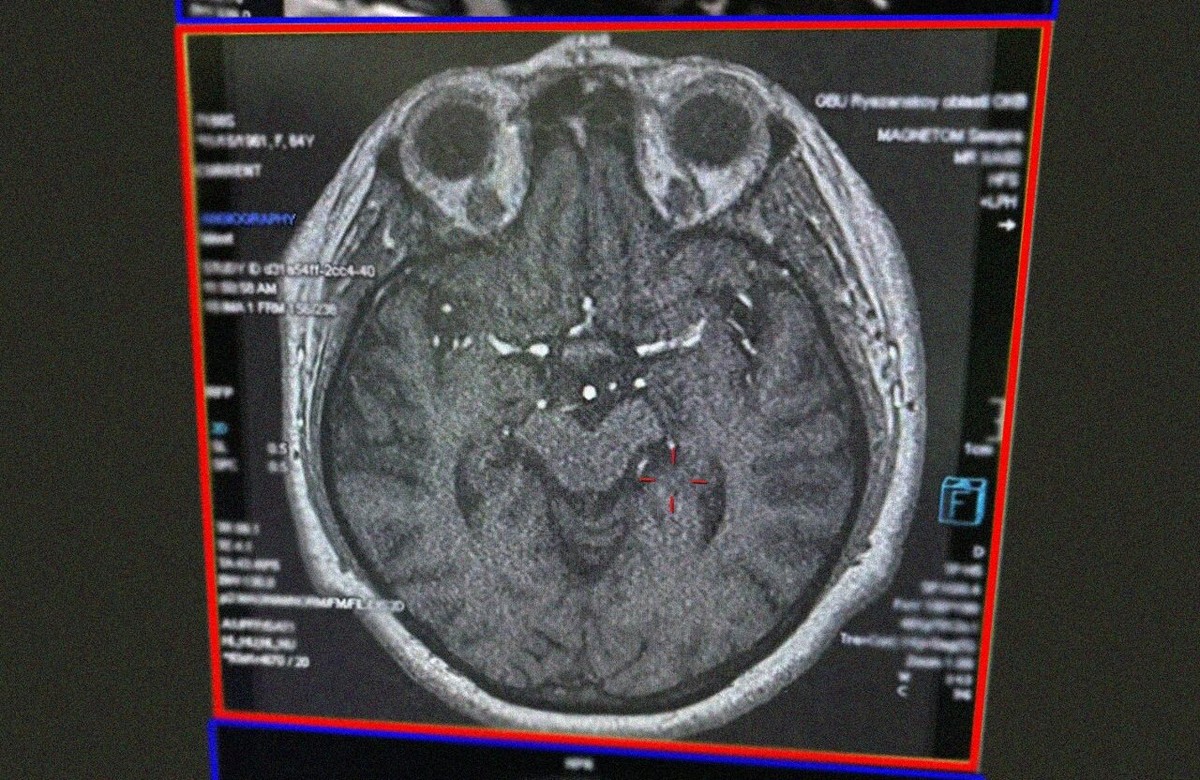

Фото: Рязанская ОКБ

Прибывшие врачи предварительно диагностировали инсульт. Пациентку госпитализировали в ОКБ. После тщательного осмотра и изучения анамнеза диагноз был подтверждён. Женщину срочно начали готовить к тромболизису.

Через девять дней её состояние значительно улучшилось. Она уже могла передвигаться самостоятельно, и её речь постепенно восстанавливалась. В ходе беседы выяснилось, что к инсульту привели её вредные привычки: длительное курение и потребление жирной, жареной и солёной пищи. Это привело к закупорке сосудов холестериновыми бляшками и нарушению кровоснабжения мозга.